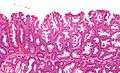

| Micrograph of a sessile serrated adenoma. H&E stain. | |

SSAs are diagnosed by their microscopic appearance; histomorphologically, they are characterized by (1) basal dilation of the crypts, (2) basal crypt serration, (3) crypts that run horizontal to the basement membrane (horizontal crypts), and (4) crypt branching. The most common of these features is basal dilation of the crypts.

Unlike traditional colonic adenomas (e.g. tubular adenoma, villous adenoma), they do not (typically) have nuclear changes (nuclear hyperchromatism, nuclear crowding, elliptical/cigar-shaped nuclei).